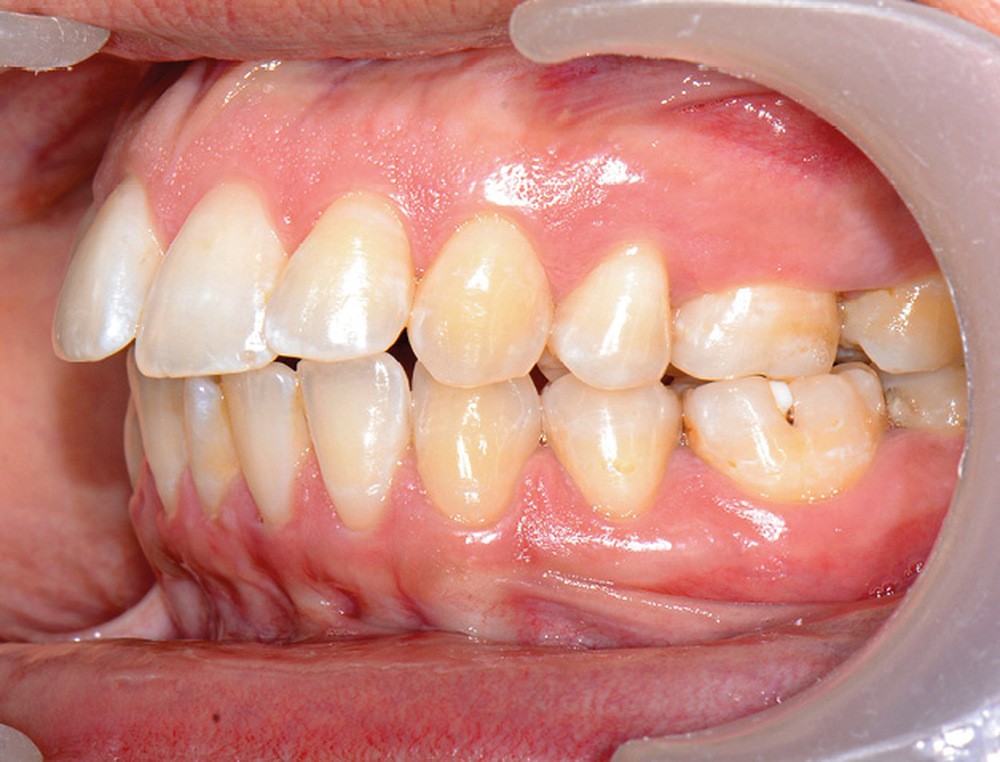

C’est précisément le cas de cette patiente de 33 ans qui présente une classe II squelettique par rétrognathie mandibulaire sur un schéma vertical hyperdivergent associée à une classe II/1 dentaire avec DDA par excès et biproalvéolie. Son profil est convexe, cis-frontal et, sur le plan fonctionnel, on peut observer une dysfonction linguale et une incompétence labiale au repos. Il en résulte une contracture des muscles de la sphère péri-orale lèvres jointes. La formule dentaire n’est pas complète puisque les quatre deuxièmes prémolaires ont été extraites lors d’un premier traitement orthodontique et qu’il y a également agénésie des troisièmes molaires 18 et 38 (fig 1 à 11).

Au regard de ces éléments, la décision thérapeutique choisie intègre une prise en charge orthodontique associée à une chirurgie orthognathique d’avancement mandibulaire et à une mentoplastie. L’étape initiale du traitement orthodontique consiste en la levée des compensations dentaires qui se traduit par la correction de la proalvéolie mandi– bulaire dans le but de pouvoir corriger la classe II squelettique et dentaire par avancement chirur- gical de la mandibule. Pour cela, des mini-vis d’ancrage sont positionnées distalement aux secteurs 3 et 4, enfouies à la base des branches mandibulaires avec des chaînettes métalliques émergentes dans la cavité buccale. L’objectif est d’assurer le repositionnement incisif mandibulaire grâce à des modules élastiques.